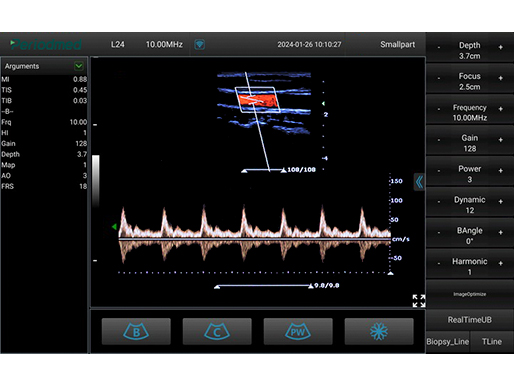

线阵探头-PW模式-颈动脉